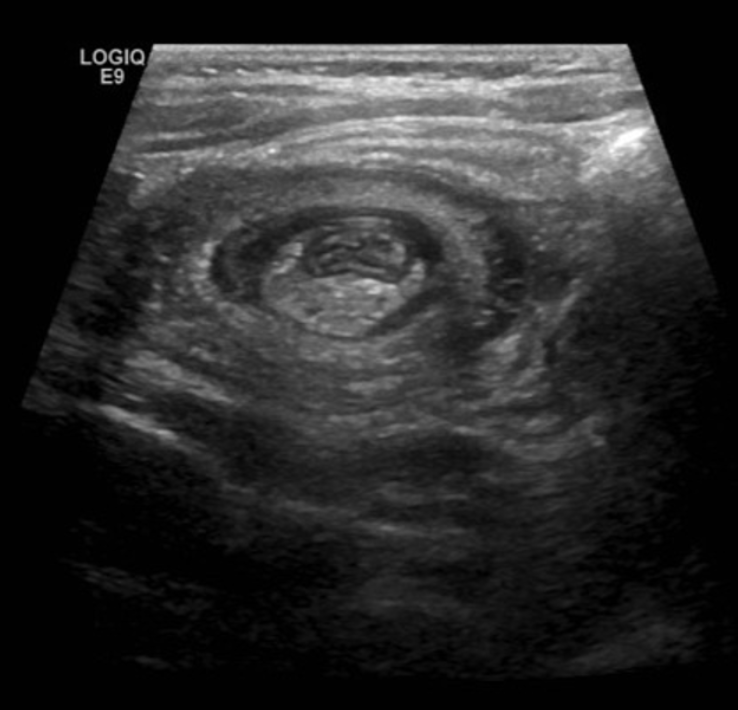

18 mon old with off/on abdominal pain X 12 hours and 1X vomit. This image is obtained. The exam may show this on abdominal exam and this on diaper exam

What is sausage mass and currant jelly stools

What is intussusception and HSP